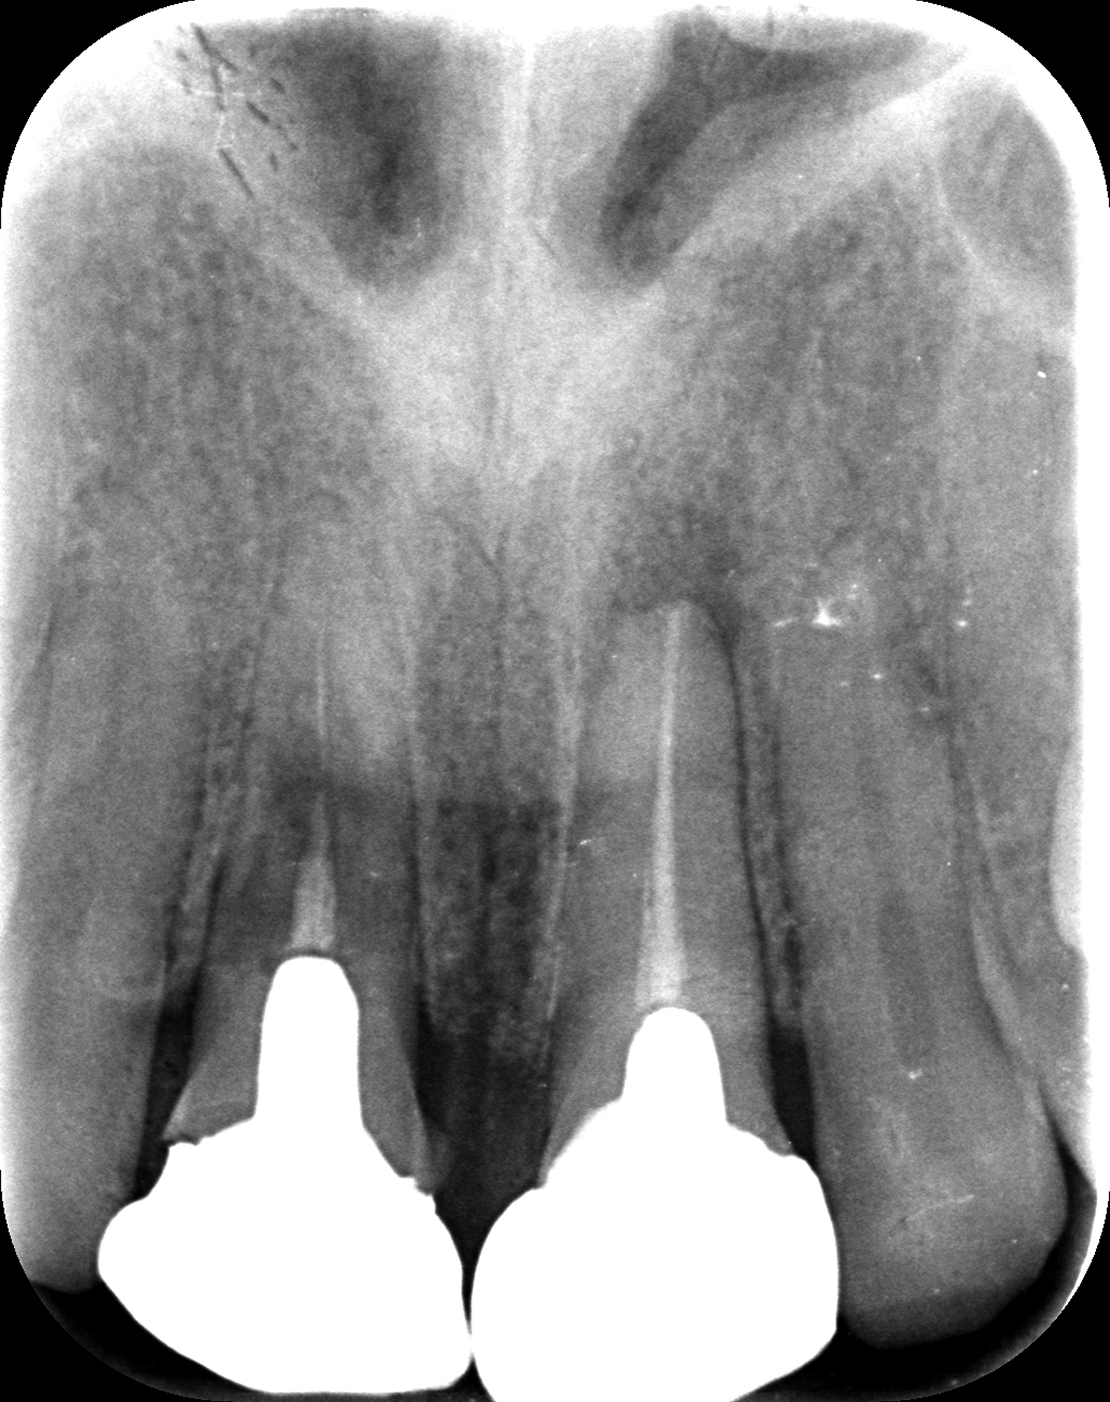

お口全体を検査したところ、自覚はありませんでしたが、右の前歯もレントゲンを見ると歯の根の中腹あたりが溶けてしまっています。この歯も残念ながら抜歯となると判断しました。